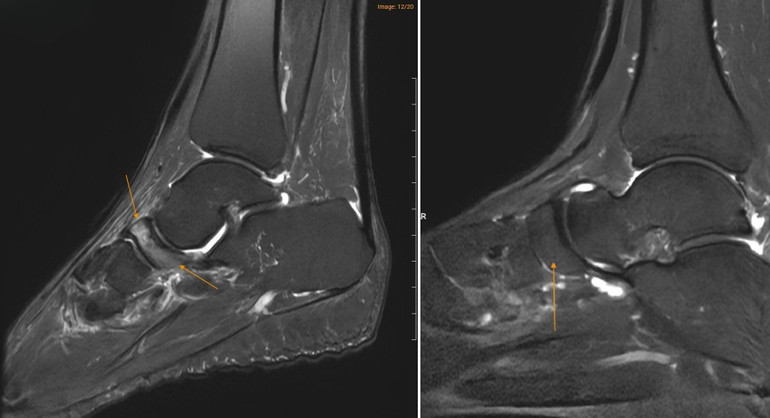

Tại Medlatec, bác sĩ đã chỉ định chụp cộng hưởng từ (MRI) để tìm kiếm những tổn thương sâu trong cấu trúc xương. Trên lát cắt Sagittal T1W, hình ảnh cho thấy xương ghe bị xẹp và biến dạng điển hình hình dấu phẩy, kèm theo tình trạng đặc xương dưới sụn. Trên chuỗi xung T2W FS, ghi nhận tình trạng phù tủy xương ghe rõ rệt.

Đồng thời ghi nhận hình ảnh tổn thương gai xương thoái hóa khớp cổ chân trái, ổ phù tủy xương vị trí xương sên, phù nề dây chằng chày mác sau, dây chằng sên mác sau, dây chằng gót chày và dây chằng tam giác cổ chân, dịch khớp cổ chân, phù nề phần mềm quanh khớp cổ chân.

Hình ảnh MRI cho thấy xương ghe ở bệnh nhân mắc Hội chứng Müller–Weiss (bên trái) có vùng sáng hơn bất thường, trong khi xương ghe ở bàn chân bình thường (bên phải) có hình ảnh đồng nhất hơn.

MRI là phương pháp nhạy nhất để phát hiện bệnh ở giai đoạn sớm thông qua tín hiệu phù tủy xương (tăng tín hiệu trên STIR/PDFS) trước khi có biến đổi về hình thái xương, đồng thời hỗ trợ đánh giá mức độ hoại tử xương.